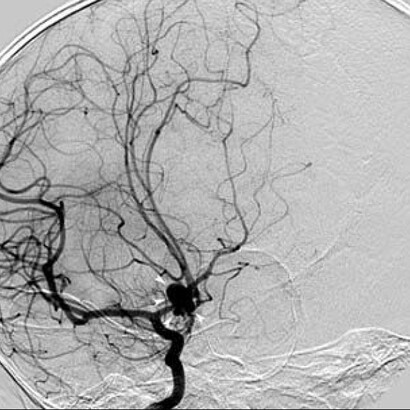

A Dios gracias, eso faltaba a la verdad. Cuando el cirujano doctor lo describió, me alegré. Un aneurisma es una falla congénita que puede suceder a cualquier edad. Es difícil de sanar, toma tiempo (mucho tiempo) y yo no contaba con ese preciado tesoro a mis 64 años.